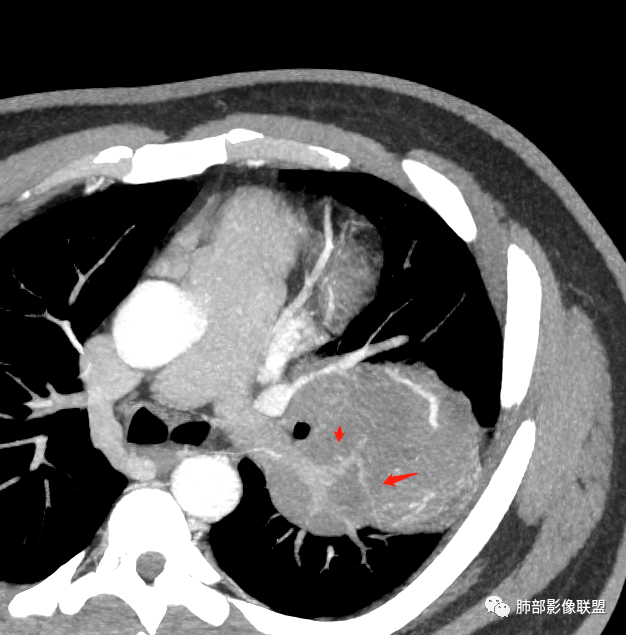

新月征很有特点,血管有特点

蛇纹血管像sft,空气新月征像psp

青年男性,体检发现左肺不规则类圆形占位性病变,叶间裂区域,定位胸膜来源。左肺下叶支气管受压狭窄,但管壁光整,未见腔内阻塞或管壁受侵。包块边界清晰,浅分叶,内部密度不均匀,病灶后份见空气新月征。渐进性强化,增强动脉期见分支状血管,蛇纹血管征。肺门纵膈未见增大淋巴结,符合孤立性纤维瘤(SFT)。

3)肺部SFT好发于肺表面如叶间裂等区域,定位相当重要。肿块边界清楚光整,支气管不受侵(或可受压推移)。CT平扫肿瘤多呈等或稍低密度。发生于脑膜的SFT平扫肿瘤多为略高密度病,类似脑膜瘤;肿瘤较小者密度均匀,较大者内部密度常不均匀、见多发灶性或不规则形中心低密度区(细胞稀疏区含有丰富胶原纤维易发生黏液样变性或囊性变),钙化少见。

5)肿瘤的强化程度及方式:增强扫描肿瘤早期实性成分呈不均匀斑片或斑驳样强化,亦可呈“ 地图样” 明显强化,强化程度不一,可呈轻度-显著强化;静脉期持续强化,多期增强及动态增强扫描均呈“快进慢出”型强化,且强化范围逐渐增大并趋均匀。肿瘤内部及周围常见多发粗细不等强化或流空肿瘤血管影。瘤体内“蛇纹血管”在其他诸如硬化性肺细胞瘤、错构瘤等等是非常罕见的。